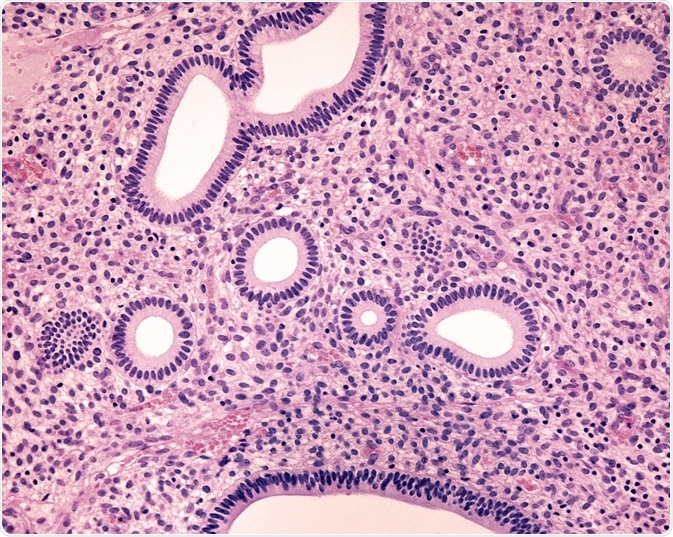

Endometrial hyperplasia (EH) is a condition in which the uterine lining is thicker than normal. It may have many causes, but the most important association is with endometrial malignancy. For this reason, it is mandatory to distinguish between different types of EH, namely, those which are benign and those which are precancerous.

Credit: Jose Luis Calvo/ Shutterstock.com